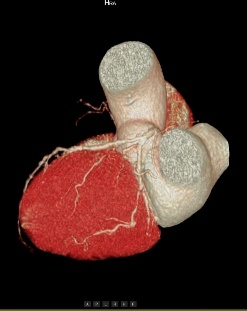

心血管成像能力方面目前

业内最好

面对高心率达到200bpm的患者,心律高度不齐、房颤、房扑的患者,都能够呈现清晰的图像质量:

(1)拥有业内最宽的16厘米探测器,轻松应对复杂心率和心律;

(2)拥有业内最全的心脏冠脉成像解决方案。

高心率+高清晰+智能分析

多维度参数评估,精准影像诊断